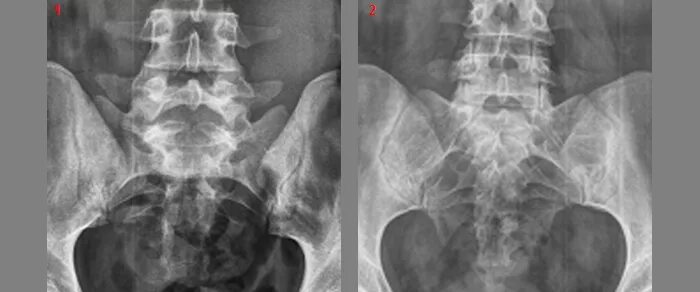

Незаращение дужки позвонка